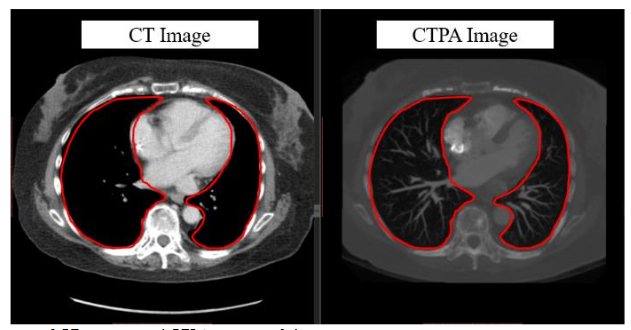

In previous research of our laboratory, it demonstrates that the deep learning model with hierarchical architecture can successfully distinguish CT scans with PE lesions and achieve high accuracy without using CTPA images, and indicates there are critical features on CT images for detecting PE. Previous proposed framework works in multiple stages on 3D lung CT scan images to detect and determine the malignancy of the nodules and also get the better result. That means CT scans have enormous potential for CT to CTPA translation. Much of the recent research employing deep learning methods for image-to-image translation has yielded significant improvements, aligning with the current trends in the field. For example, in medical imaging, the translation of images from Magnetic Resonance (MR) to Computed Tomography (CT) stands as a notable application of deep learning for medical image synthesis and continues to be one of the most frequently published topics in this domain. Since the main difference between CTPA image and CT image is the characteristic of the contrast agent, and both have similar cross-section shown in

, we can regard CT to CTPA translation as an image style conversion task.